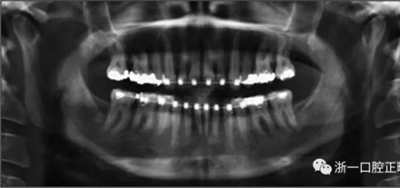

術后第9天開始旋轉擴弓器,每天轉2次,每次轉90度,即擴開0.5mm。每隔1周進行檢查,目標上頜擴開9mm,下頜擴開6mm。18天后,上頜中切牙間出現8mm間隙。下頜出現6mm間隙,(于13天出現后,停止旋轉擴弓器)。在擴弓器旋轉3天后,拍片發(fā)現左下頜中切牙遠中牙根中段有一條低密度陰影,臨床冷熱診反應遲鈍,可能為術中損傷所致。牙體牙髓科會診,建議行根管治療,故行根管治療。

擴弓保持8周后,除擴弓器影響牙外粘接托槽,使用0.014鎳鈦絲進行排齊、整平。旋轉停止后3個月拆除擴弓器,全口粘接托槽,使用0.016niti繼續(xù)排齊整平。佩戴可摘保持器,保持上頜寬度。在使用至0.018x0.018niti7周,徹底排齊整平后,使用大弓型的0.016x0.022不銹鋼絲,繼續(xù)維持原有寬度,同時停止使用可摘保持器。掛II類牽,糾正磨牙關系,使用鏈圈關閉散在間隙,少量使用IPR去除局部前牙的黑三角。術后9個月拍全景示,牙根平行度可,再無其他牙根出現問題。1年7個月后治療結束。上下頜3-3舌側保持器+哈雷氏保持器進行保持。